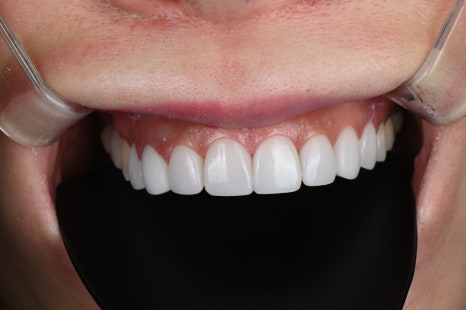

시술명 : 라미네이트

왼 : 시술 전 / 오 : 시술 후 5일 경과